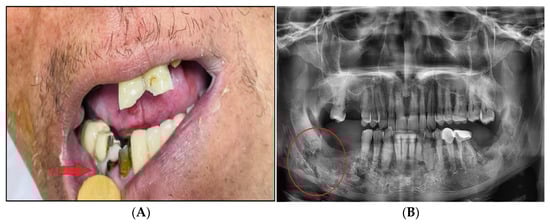

3.8. Osteoradionecrosis (ORN)

Osteoradionecrosis (ORN) refers to ischemic bone necrosis that is not healing due to RT exposure (Figure 7). It is characterised by soft tissue necrosis and may last three months [7,42]. The history of ORN goes back 100 years to when it was first noted in 1922 by Regaud. ORN is uncommon (5–15% only) but can have a significant negative influence on QoL [65,66]. Modern RT techniques can lower the ORN risk of occurrence. In this review, ORN prevalence was 7.4% with conventional RT, 6.8% with chemoradiation, 5.3% with brachytherapy, and 5.1% with IMRT [9]. A newer study showed the lowest incidence of ORN with proton RT compared to IMRT, 2% vs. 7.7%, respectively [67]. In addition to the selective suppression of osteoclasts in radiated bone, the pathophysiology of ORN is attributed to the concept of “three-H-H-H” (hypocellularity, hypervascularity, hypoxia) of bone that is caused by RT [68]. Subsequent trauma (primarily dental extraction) or spontaneous disruption of the oral mucosa will then be associated with a significant amount of bone fibrosis and damage to the remodeling system (osteocytes, osteoblasts, and osteoclasts) [69]. These alterations eventually result in a non-healing process that can lead to necrosis with or without infection [8,11,68].

Figure 7.

After receiving radiation therapy, a male patient with HNC developed osteoradionecrosis, which is defined as bone necrosis combined with soft tissue necrosis (A) and osteoradionecrosis on an X-ray (B).